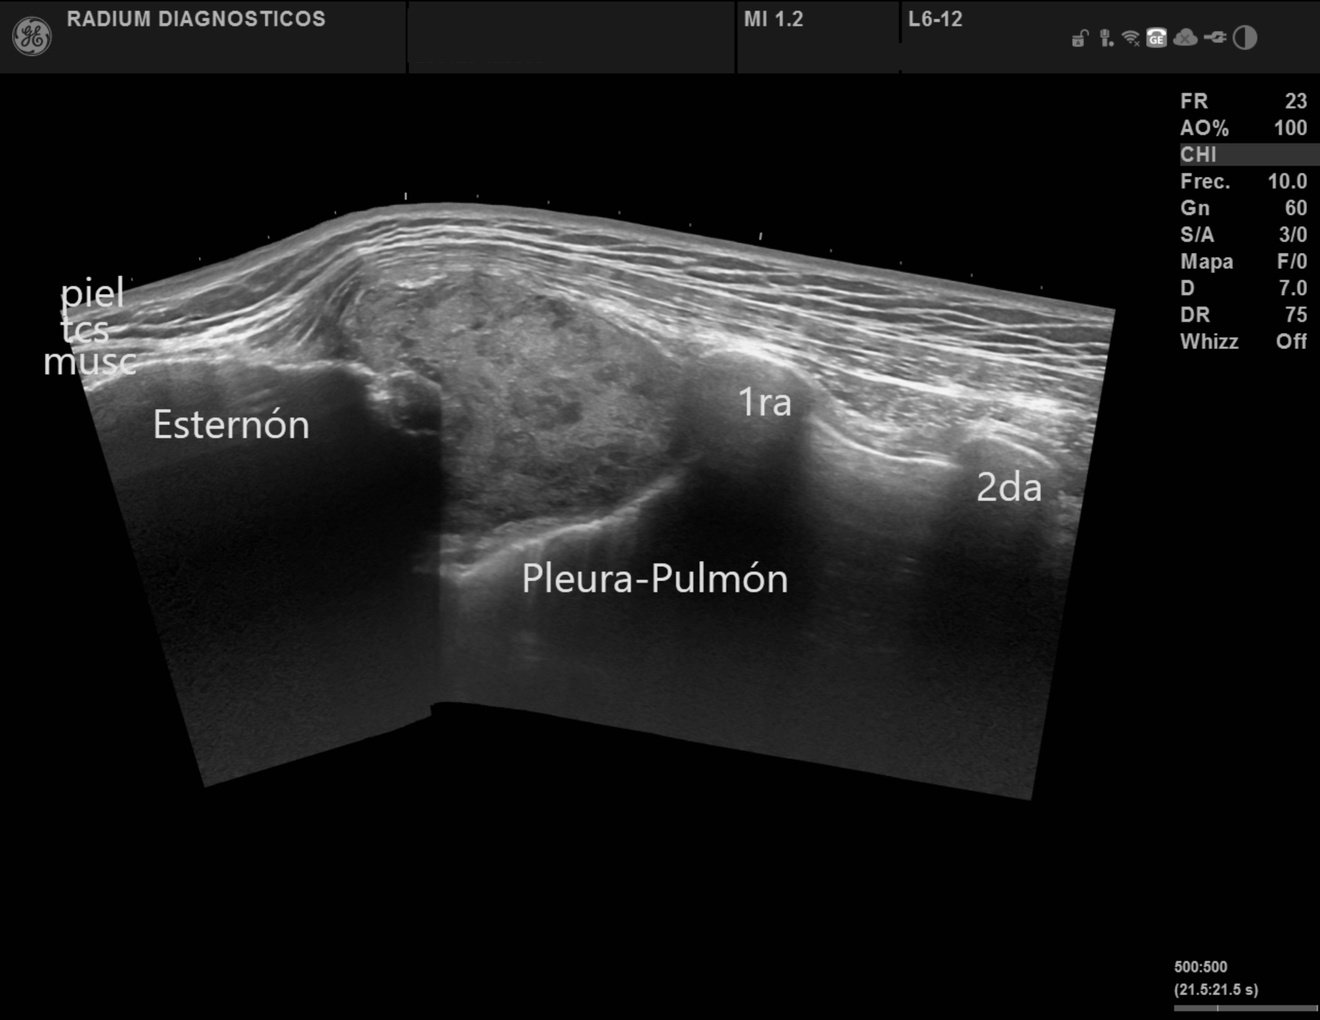

En centro de Imagen Radium ofrecemos estudios de Radiología e Imagen Médica de alta precisión a un precio justo, con equipos de última generación.

Imágenes de Alta Precisión.